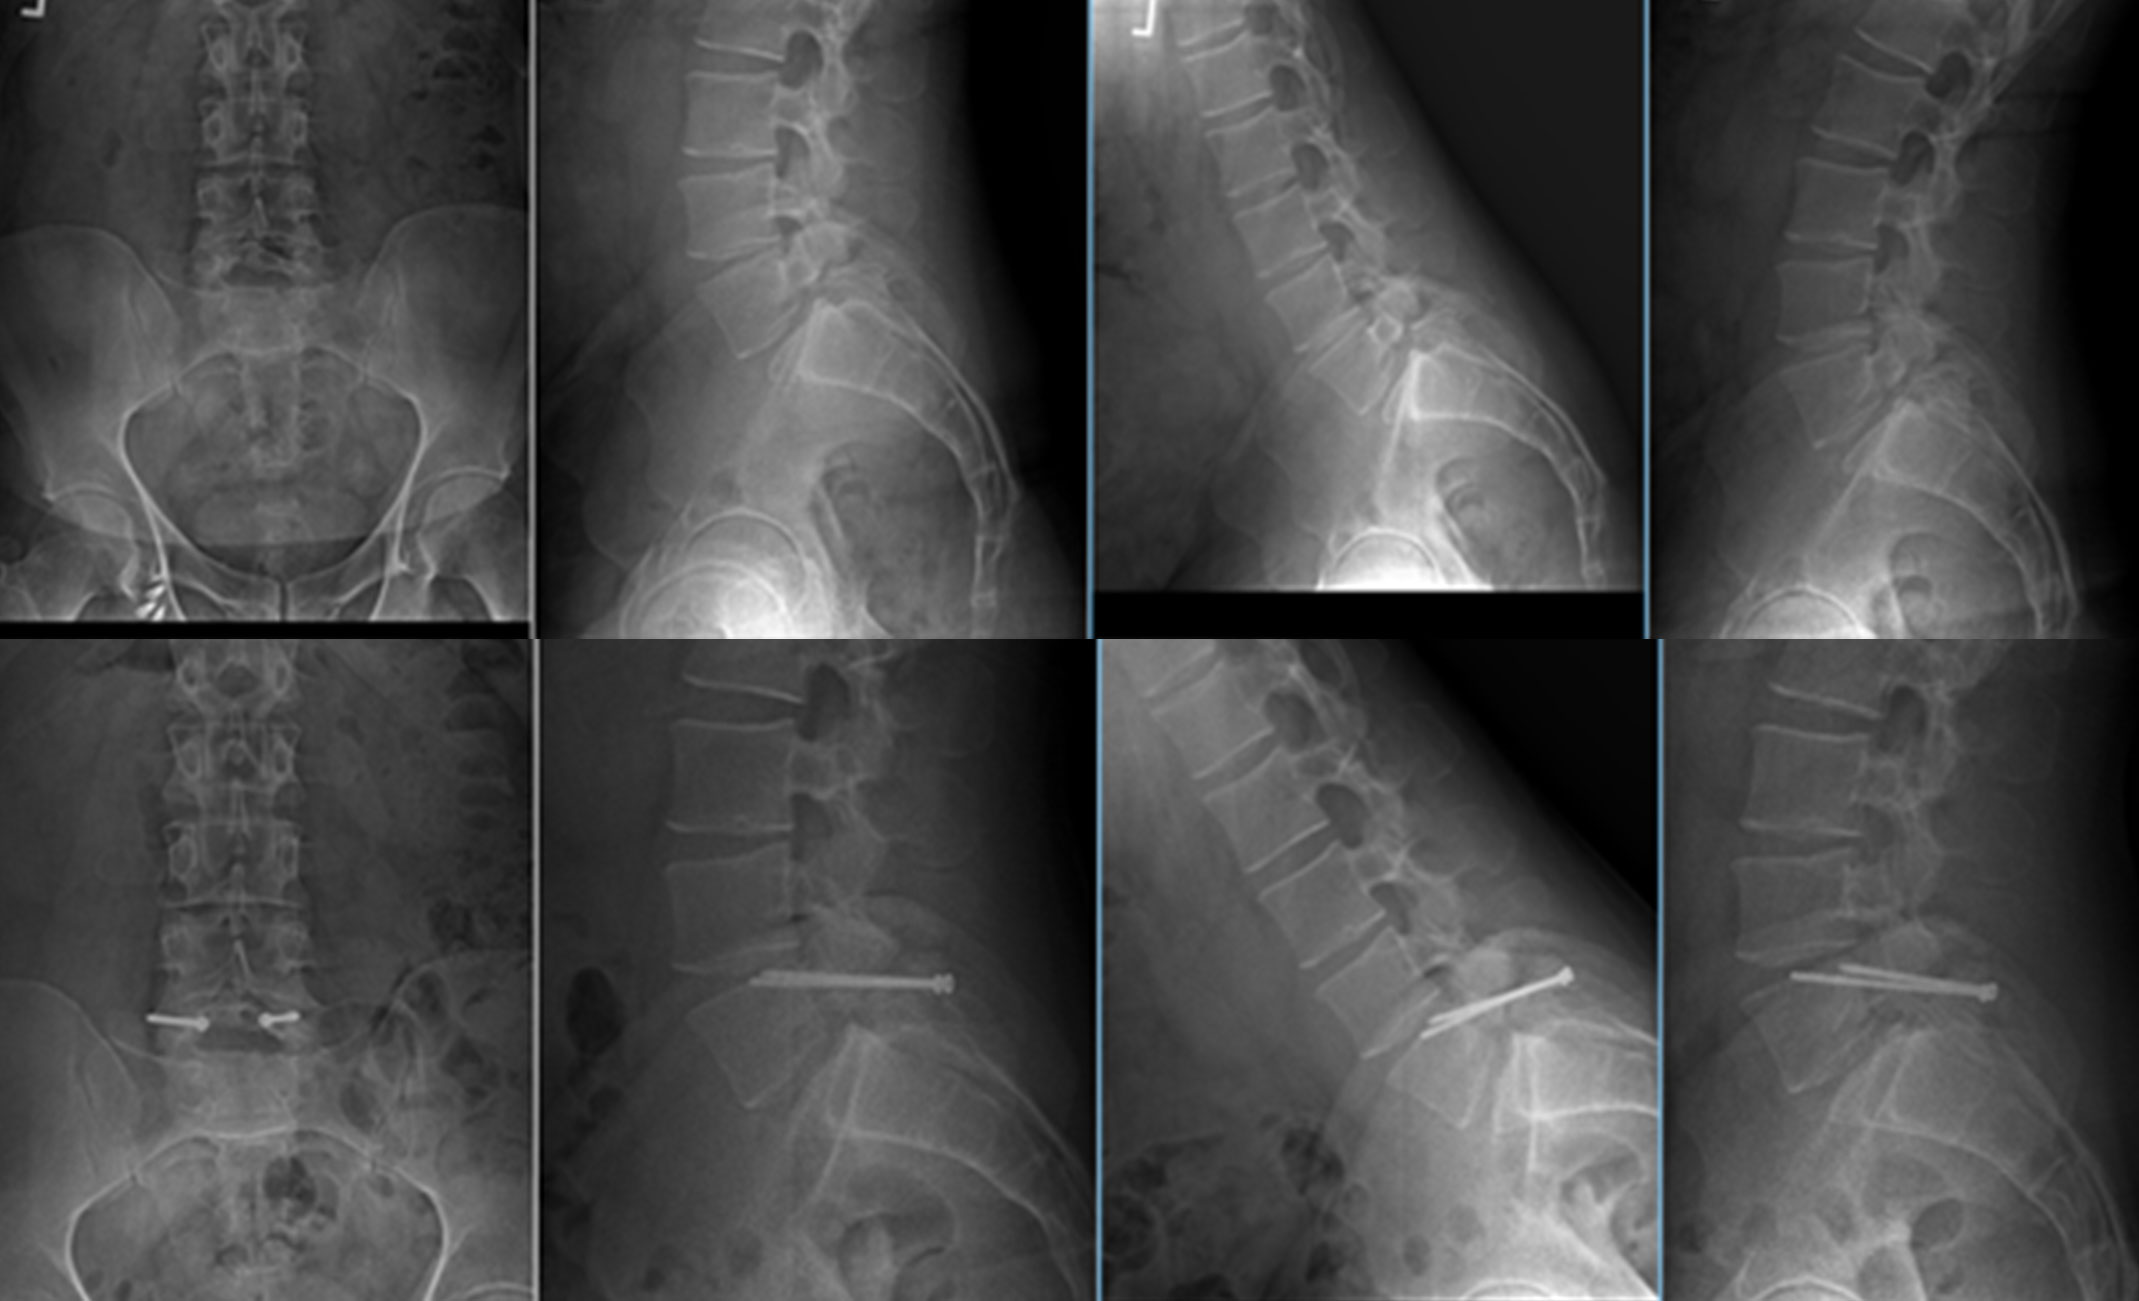

X-rays of Patient With Spondylolisthesis Before and After Pars Repair

(Top) X-rays from different angles of a 34-year-old spondylolisthesis patient with a painful low-grade slip (blue arrow) after a jet ski accident. (Bottom) After pars repair, the patient's pain has improved and motion is preserved.

Images courtesy of Maahir Haque, MD, FAAOS